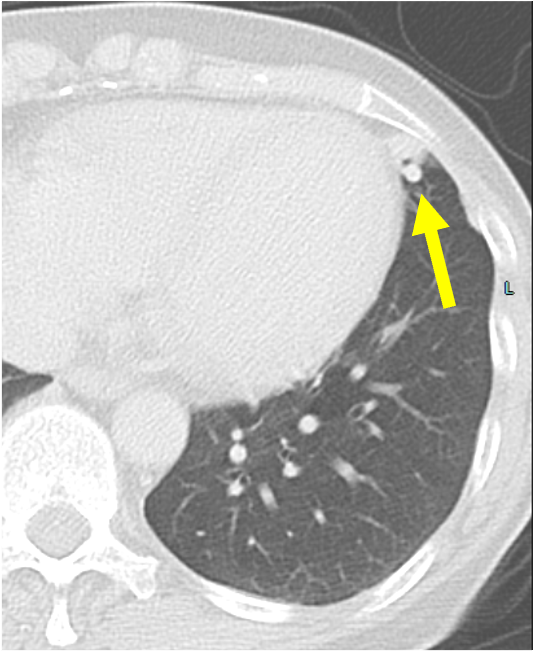

肺動静脈奇形は肺動脈・静脈が正常の毛細血管を介さずに短絡する血管奇形であり、肺動静脈瘻と呼ばれることもある。臨床症状としては低酸素血症や喀血、稀に血胸を示す。また、脳膿瘍や奇異性脳梗塞などの合併症を伴う可能性が知られている。しかし無症候性に肺結節として偶発的に指摘される例も少なくない。流入動脈、流出静脈がともに1本の場合をsimple type、複数の場合をcomplex typeと分類する。

造影CTでは肺動脈と同等の強い造影効果を呈し、単純CTに比して詳細な評価が可能となる。動静脈奇形の大きさ、流入動脈・流出静脈の数や吻合の位置をあらかじめ確認することで、治療計画に有用である。また、3D画像を再構成することでより立体的に形状を把握することができ、任意の方向から画像を観察することで塞栓時のアクセスルートを決定する一助となる。